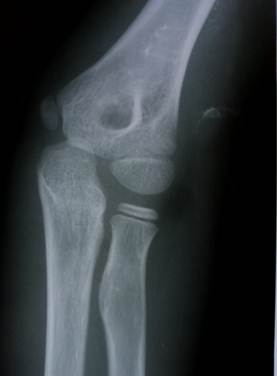

Область локтя в разном возрасте

Василий Оскарович Маркс говорил, что неподготовленный человек на

снимке локтевого сустава здорового ребенка найдёт восемь переломов. Очень даже

может быть – рентгенологическая картина локтя ребенка в возрасте от года до

четырнадцати лет насыщена ядрами окостенения и зонами роста, которые легко

принять за костный отломок или осколок, особенно если в анамнезе есть травма.

1 год - 3 года

В возрасте года выявляется булавовидный метафиз плечевой кости,

ядро окостенения головчатого возвышения и латерального вала блока.

Верхний конец лучевой кости отстоит от уровня щели локтевого сустава

достаточно далеко. Конец локтевой кости находится на уровне суставной щели. К 3

годам на снимках очерчивается основание головки лучевой кости и хорошо видна

блоковидная вырезка локтевой кости с основаниями локтевого и венечного

отростков. В самом конце периода появляется ядро окостенения головки лучевой

кости.

Прямой снимок локтевого сустава ребенка 5 месяцев. Обратите

внимание, насколько далеко отстоят друг от друга видимые,

т.е. окостеневшие части сочленяющихся костей.